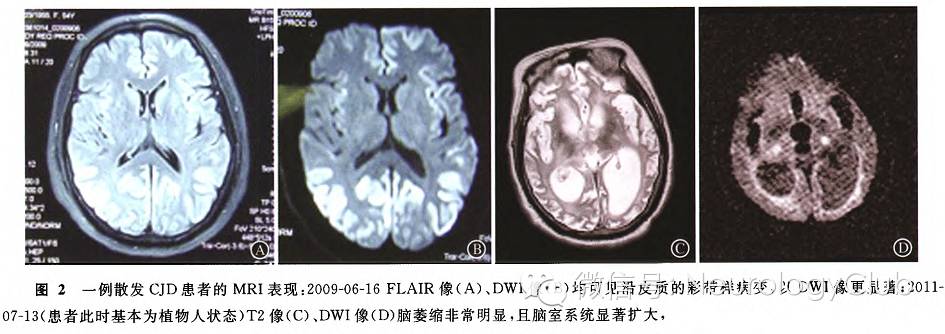

CJD典型三联征为:进行性痴呆、共济失调、肌阵挛临床表现大体可分为三个阶段:早期以乏力、疲劳、注意力不集中、记忆减退等为主要表现;中期(痴呆-痉挛期)表现为记忆障碍、性格改变、痴呆,可伴失语、失认,2/3患者出现肌阵挛,大脑皮质、锥体外系、锥体束及小脑受损的症状交替或相继在此期出现;晚期表现为尿失禁、无动性缄默或去皮质强直。诊断主要根据迅速进展的近记忆障碍,无感染症状,影像学特别是DWI和FLAIR像上常可见沿着大脑皮质有彩带样病变(ribbon-like lesion),这是极具特征的表现(图2A、B)。但是疾病后期患者脑组织萎缩极其严重,脑室扩大,彩带样病变也不再明显(图2C、D)。CJD患者CSF中也可能出现一定数量的白细胞,如CSF检查有10-30个白细胞的存在时,不要误认为该患者一定是病毒性脑炎或其他感染。目前对于CJD尚无治疗方法。但也不必担心该病患者对正常人的传染,至少到目前为止,国内尚未见患者与家人及医务人员之间通过一般性接触传播的案例。